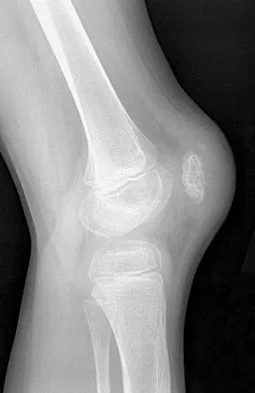

Figures 12a and 12b show the radiographs of a 50-year-old patient who reports acute knee pain after sustaining a twisting injury while playing tennis. Examination is unremarkable. The next most appropriate step in management should consist of

Explanation

The radiographs show localized diffuse cortical thickening that is characteristic of melorheostosis. The condition may be monostotic or it may involve many bones in one extremity (monomelic) in the distribution of a sclerotome. Bone scans will show increased uptake at the site or sites of skeletal involvement. Long tubular bones are most commonly involved. Melorheostosis is usually asymptomatic and requires no treatment. On rare occasions, there may be associated soft-tissue contractures. Dorfman H, Czerniak B: Bone Tumors. St Louis, MO, Mosby Inc, 1998, pp 1105-1107. Campbell CJ, Papademetriou T, Bonfiglio M: Melorheostosis: A report of the clinical, roentgenographic, and pathological findings in fourteen cases. J Bone Joint Surg Am 1968;50:1281-1304.